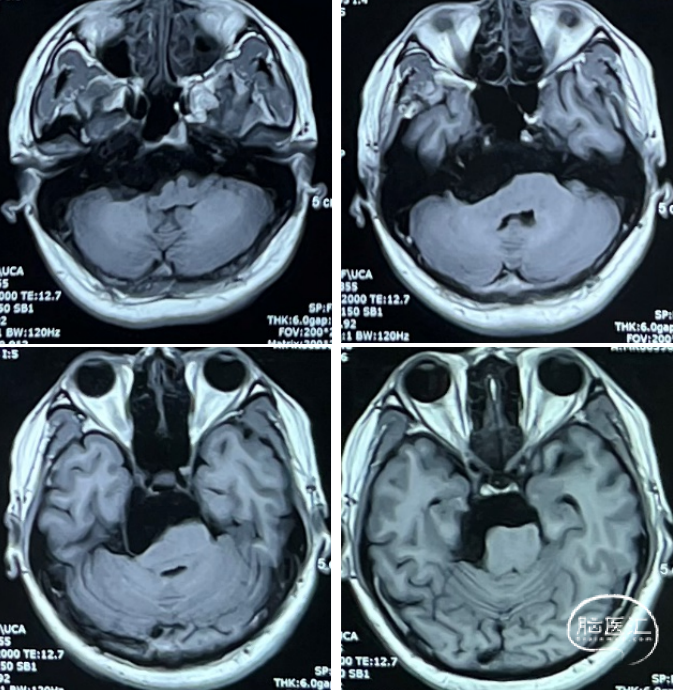

术后MRI